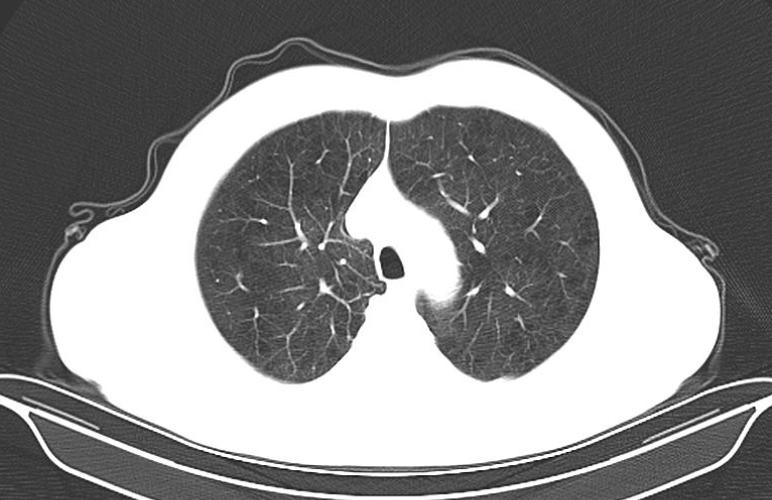

白色粗线就是条索

条索,在CT图像上形态类似条索状样的高密度影,说的通俗点,CT图像上的线状或者粗条状的白影就是条索。它是如何形成的呢?通常是由于成纤维细胞增生,导致纤维化,说的简单点,是因为之前肺部有炎症,现在已经痊愈,条索就是愈合后遗留下来疤痕。所以说,CT报告单上有少许条索,不必过于紧张。当然,肺间质纤维化患者会出现双肺多发粗大的条索,肺结核和一些肺部肿瘤的周边也会有条索的出现,因为这些病变同样会刺激成纤维细胞的增生,出现条索。

高频词汇三:肺大泡

肺是由多个肺泡组成的,每个肺泡都好像一个有弹性的气球,能储存氧气,排出二氧化碳。肺大泡呢,一般继发于小支气管的肺炎或者是肺气肿,肺泡壁及间隔逐渐因泡内压力升高而破裂,肺泡互相融合形成大的含气囊腔,就像一个充满残气的塑料袋,失去了弹性。肺大泡在CT上是黑色空腔,壁细薄,多为圆形、椭圆形,大小不一。老烟民的肺部常常有很多的肺大泡!小的肺大泡本身不引起症状,有些肺大泡可经多年无改变,有些肺大泡可逐渐增大,或在其他部位又出现新的肺大泡,甚至部分肺大泡发生融合,这种情况要警惕了,因为巨大肺大泡可使肺功能发生障碍,还会有胸闷、气短的临床表现,若肺大泡突然增大破裂,可产生自发性气胸,而引起严重的呼吸困难。